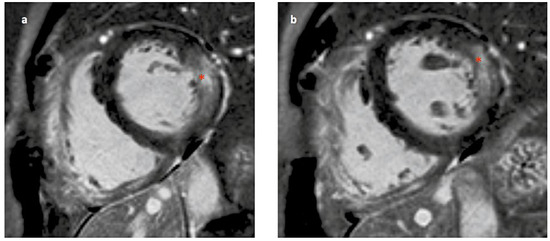

Fabry disease – a rare but important cause of left ventricular hypertrophy. Fabry disease (synonym: Morbus Fabry, Anderson Fabry disease) is an Xlinked lysosomal storage disease due to a deficient activity of alpha-galactosidase A. This leads to pathological glycosphingolipid metabolism, resulting in deposition [...] Read more.

Fabry disease – a rare but important cause of left ventricular hypertrophy. Fabry disease (synonym: Morbus Fabry, Anderson Fabry disease) is an Xlinked lysosomal storage disease due to a deficient activity of alpha-galactosidase A. This leads to pathological glycosphingolipid metabolism, resulting in deposition of glycosphingolipids in lysosomes and body fluids. There is evidence that the glycolipids also accumulate extralysosomally, which is a very important factor in the pathogenic impact. Cardiac involvement is one of the most important disease manifestations because the patients mainly die from cardiac complications. There are two phenotypes: classic and later-onset. First symptoms of the classic phenotype occur during the childhood and include angiokeratomas, hypohidrosis, cornea verticillata, and tortuosity of conjunctival and retinal vessels. Young patients typically suffer from acroparaesthesias, abdominal cramping and pain crises. With advancing age, the progressive sphingolipid deposition, particularly in the endothelial cells, cardiomyocytes and podocytes, leads to arterial hypertension, cardiomyopathy, nephropathy and premature strokes. In contrast to the classic phenotype, patients with the later-onset phenotype lack the early disease symptoms. They typically present to the hospital in adulthood with cardiomyopathy or with nephropathy. In females, alpha-galactosidase A activity can range from low to normal owing to random X-chromosome inactivation. Generally, females have a milder phenotype because of the second, unaffected X-chromosome. Patients with Fabry cardiomyopathy suffer from left ventricular hypertrophy, conduction abnormalities and valvular involvement, as well as from diastolic and/or systolic heart failure symptoms. The enzyme activity determination in leucocytes is diagnostic in males but can be misleading in females owing to random X-chromosome deactivation. Thus, genetic testing is suitable for the diagnosis in females and should also be performed in males for the confirmation of the diagnosis. Since 2001, intravenous enzyme replacement therapy has been available for the treatment of patients with Fabry disease. Since 2016, oral pharmacological chaperone therapy has been available for patients with amenable mutations. Substrate reduction and gene therapies are currently in development. Full article

Show Figures

Figure 1